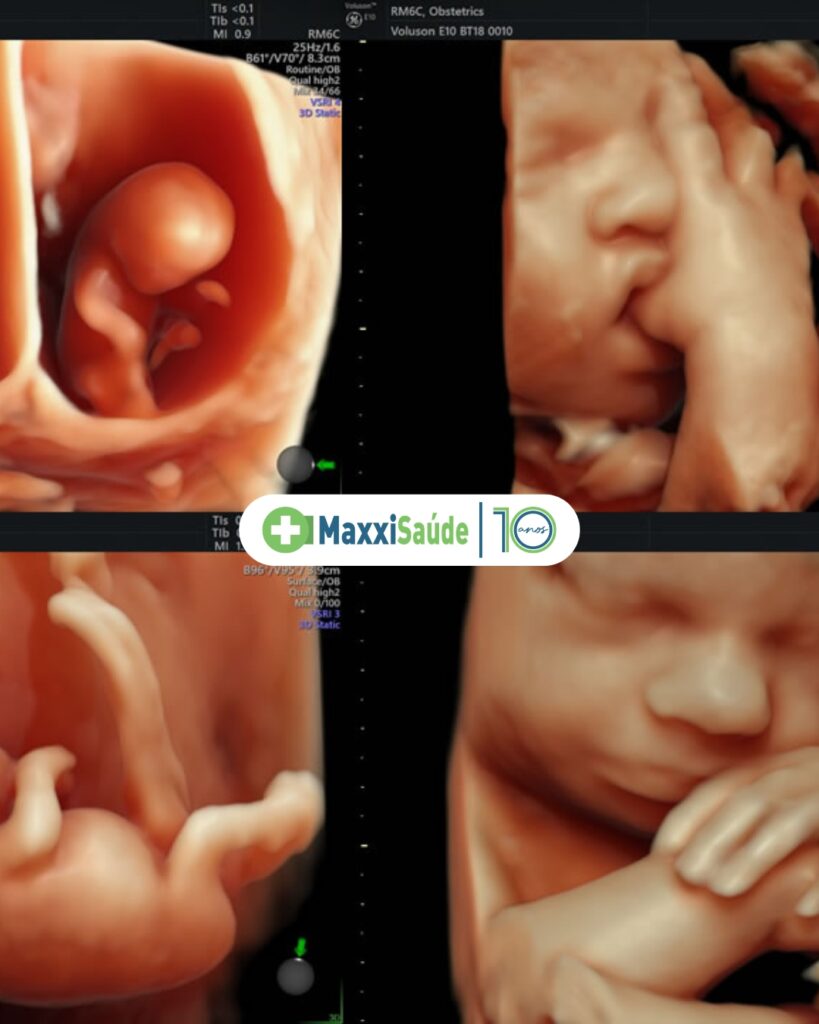

O ultrassom morfológico é um exame de imagem realizado durante a gestação com o objetivo de avaliar detalhadamente a anatomia do bebê. Diferente do ultrassom obstétrico comum — que acompanha o crescimento e o bem-estar fetal —, o morfológico é um exame mais completo e minucioso.

Por meio dele, o médico analisa estrutura por estrutura do bebê: cérebro, coração, coluna, rins, membros, face, abdômen e muito mais. É como uma “visita guiada” ao mundo do seu filho ainda dentro do útero.

Este é o exame mais completo e aguardado pelas mamães. Nele é possível avaliar com muito mais detalhes:

- Coração fetal — estrutura das câmaras e válvulas

- Cérebro e sistema nervoso central

- Face — lábio, palato, olhos e nariz

- Coluna vertebral

- Rins e vias urinárias

- Membros superiores e inferiores

- Placenta, líquido amniótico e cordão umbilical

- E, claro, muitas vezes o sexo do bebê

Contamos com equipamentos de ultrassonografia de alta resolução, que permitem imagens nítidas e detalhadas, fundamentais para uma avaliação morfológica completa e confiável. Nossos exames são realizados por profissionais especializados, com experiência em medicina fetal, que conduzem cada atendimento com atenção, paciência e acolhimento.